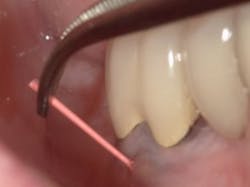

Floss threaders come in two basic styles: plastic loops and prethreaded. Plastic loops are sturdy but may be too large for tight spaces—lower lingual retainers placed too close to the tissues or impenetrable implant bridge come to mind. On the other hand, prethreaded versions are fragile and break easily, rendering them useless and requiring a new piece. Cotton pliers can assist in guiding the threaders and giving extra reach. If you trust the patient, those who have trouble threading may benefit from a pair of pliers for home use.Chronic dental infections, trauma, and dental implant complications can lead to dental fistulas.3 Fistulas are tracks of infection that originate from a source and extend to the surrounding soft tissue, dissecting through the path of least resistance.3 The head will look like a pimple and its presence should immediately trigger further investigation.

Most fistulas are endodontic or periodontal in nature. The appropriate specialist referral is possible with endodontic gutta percha (GP) points. As they appear radiopaque on x-rays, threading an open fistula can help confirm the origin of its source. Every office should have a vial of 30-gauge GP for this reason. First, break the point in half so that during an x-ray the patient does not accidentally bite down on it. Using cotton pliers, gently guide the point through the fistula until there’s resistance. A radiograph can then be used to determine the next course of action. Don’t be fooled and assume the source. Many times, a GP point will veer off in a surprising direction.